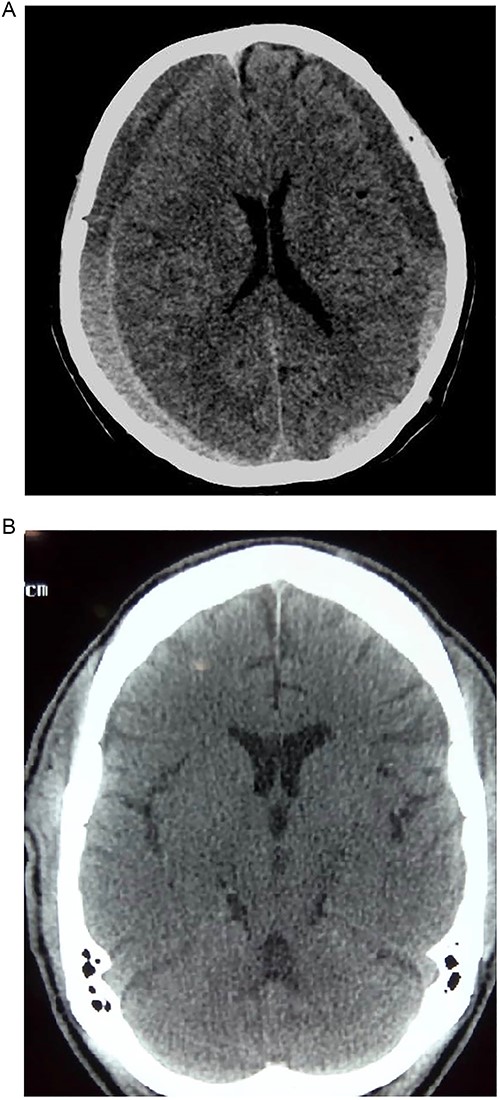

Prior to this, he had been managed for low back pain and lumbar spondylosis. Spine MRI done prior to neurosurgery consultation did not explain the lower extremity motor weakness. Brain CT done revealed bilateral fronto-parietal CSDH (Fig. 2A). He was worked up for urgent surgical evacuation through a bilateral frontal and parietal burr hole drainage. He made good neurologic improvement and his lower extremity power returned to normal on the 8th day post op. Post-operative CT scan done at 4 weeks follow-up showed satisfactory resolution of the haematoma (Fig. 2B).

(A) Pre-op showing bilateral CSDH. (B) Post op complete resolution of CSDH.